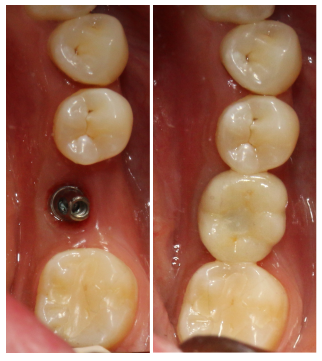

2017年9月30日 46二期+取模。

2017年10月24日46戴牙